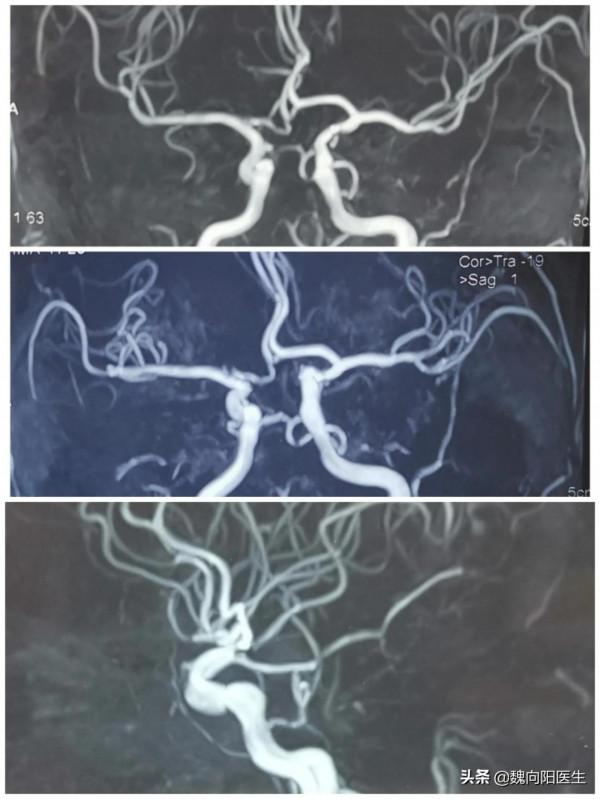

雙側椎動脈造影均未發現大腦後動脈,雙側頸動脈造影發現雙側的胚胎性大腦後動脈。

頸內動脈岩骨段發出永存三叉動脈,並與基底動脈相連,代償及基底動脈遠端及雙測小腦上動脈。

考慮患者是先天發育異常,顱內腦血管血運良好,沒有明顯缺血癥狀,並沒有做血管支架的指徵。